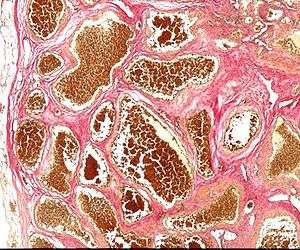

Central nervous system cavernous hemangioma is a cavernous hemangioma that arises in the central nervous system (CNS). It can be considered to be a variant of hemangioma, and is characterized by grossly large dilated blood vessels and large vascular channels, less well circumscribed, and more involved with deep structures, with a single layer of endothelium and an absence of neuronal tissue within the lesions. These thinly walled vessels resemble sinusoidal cavities filled with stagnant blood. Blood vessels in patients with cerebral cavernous malformations (CCM) can range from a few millimeters to several centimeters in diameter. Most lesions occur in the brain, but any organ may be involved.[1]